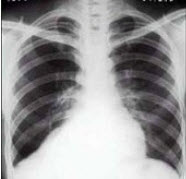

10、单项选择题

男性,45岁,有糖尿病史,突起寒战、高热,咳嗽,快脓性痰,伴胸痛2天,X线显示双肺实变,其中可见多个液气囊腔(如图),最可能的诊断是()

A.葡萄球菌肺炎

B.肺炎支原体肺炎

C.肺炎链球菌肺炎

D.肺炎衣原体肺炎

E.病毒性肺炎